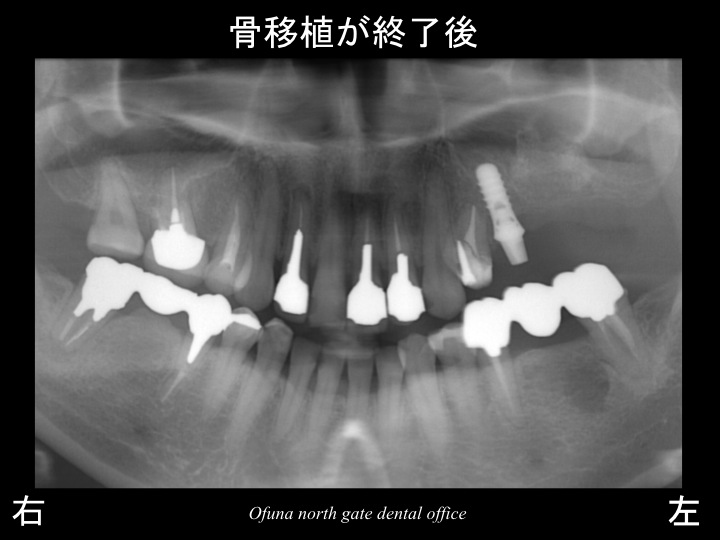

以下がサイナスリフト法(上顎底挙上術) 後です。

先に埋入したインプラントの後方が白っぽく見えると思います。

これが、移植した骨(人工骨とのミックス)です。

分かりやすくするために、サイナスリフト法(上顎底挙上術) 前後を線で書いてみましょう。

以下の緑線が治療前の上顎洞の位置です。

黄色線が骨移植後の上顎洞の位置です。